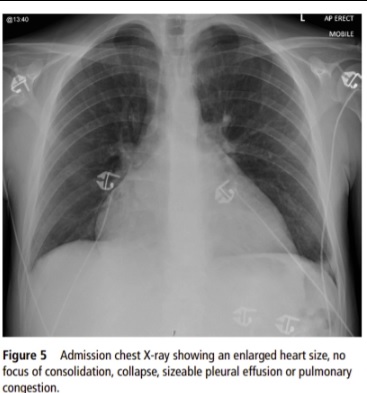

Xét nghiệm máu, chụp cắt lớp và điện tâm đồ cho thấy thanh niên bị suy tim và suy thận, trong đó suy thận được gây là bởi một tình trạng khác, còn suy tim được các bác sĩ cho là do uống quá nhiều nước tăng lực.